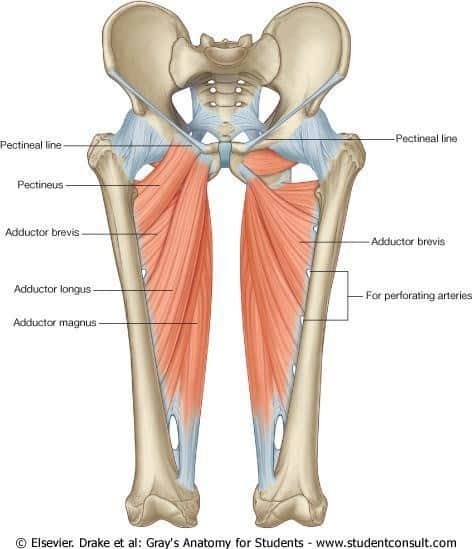

Your adductors (or groin muscles) are the group of muscles running along your inner thigh. They run from your lower pelvis to the medial part of your femur, or thigh bone [1].

In their basic anatomical function, your adductors work to bring your leg in toward the midline of your body. However, their function gets a lot more complicated as your body starts to move around in space.

For one, your adductors work to keep your pelvis in line when you stand and walk. They also fire as you cut and change direction, and during flexion and extension of the thigh [2].